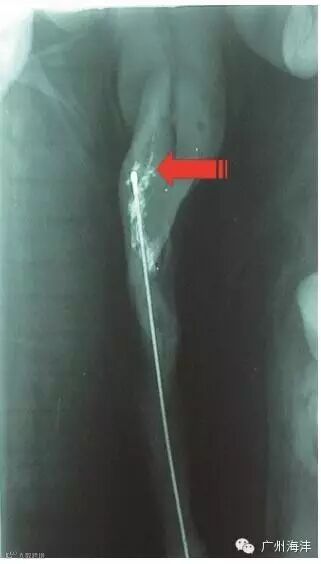

100%全新医用材料,经产输精管+细管+锁紧装置,泡沫头预润滑

泡沫头顶部不会刺伤母猪生殖道

完美卡位子宫颈,避免精液回流

100%新料,输精管韧性好,不易折断